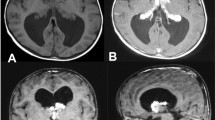

A 1-year-old patient, product of preterm gestation because of premature rupture of membranes, and previously healthy, presents with vomiting and irritability. Communicating hydrocephalus is evident in computed tomography (CT); VPS is placed, and 45 days after surgery, the patient developed ascites. CT abdomen shows free fluid in the cavity, without a solid or hollow viscera lesion. VPS is externalized, reporting drainage volumes of 1000–1200 ml/day of CSF, without signs of infection. Given such high output, magnetic resonance imaging (MRI) is performed showing bilateral CP hyperplasia (Figs. 1 and 2). The bilateral endoscopic procedure is performed in 2 stages: first, only CP cauterization (CPC). Subsequently, CSF flow decreases by 800 ml/day, and bilateral plexectomy was performed using a right frontal approach and performing a posterior septostomy, decreasing CSF outflow to 120 ml/day. It is decided to install VPS. A biopsy confirmed the diagnosis of CP hyperplasia.